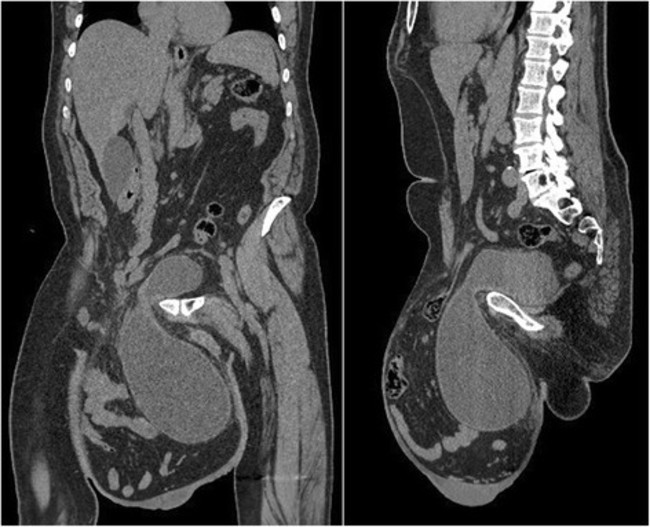

A MOROCCAN MAN had a hernia the size of a football removed from his scrotum after it became so large he couldn’t walk.

The man had been diagnosed with a giant inguinoscrotal hernia, an extremely rare condition which appears only after years of neglect or the lack of an accessible surgical facility.

He reported a large swelling that was gradually getting bigger and had reached below the level of his mid-thigh. He also described episodic abdominal pain and increasingly difficult urination.

Hernia Tarchouli et al. Journal of Medical Case Reports 2015 Tarchouli et al. Journal of Medical Case Reports 2015

Massive hernia Tarchouli et al. Journal of Medical Case Reports 2015 Tarchouli et al. Journal of Medical Case Reports 2015

Doctors said the hernia was around 30cm in diameter, around the size of a football.